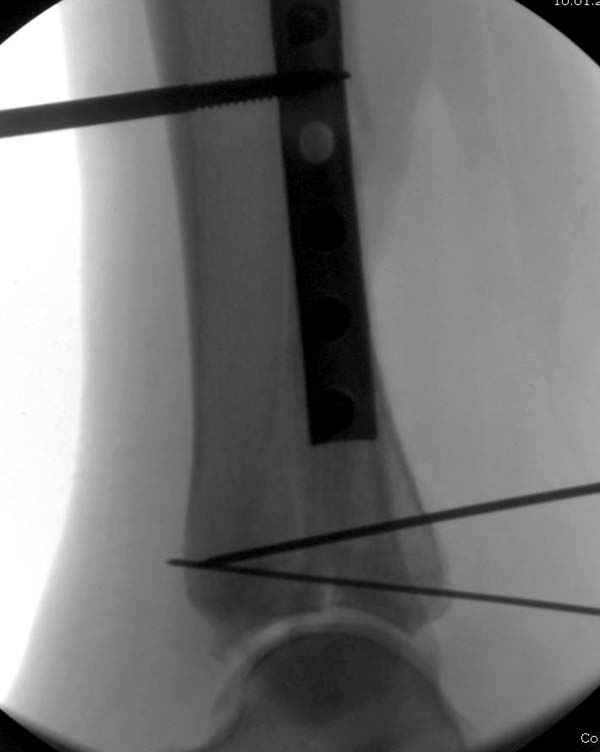

Из заднего доступа остеотомия тонким остеотомом и коррекции на ЭОПе.

Без применения сложной конструкции, а обычными параллельными шурупами. Шурупы в 3.5 мм и дополнительно фиксация крючковидной пластиной, сделанной из 3.5 mm semitubular пластиной, Butress или аntiglade фиксация.

Здесь алгоритм фиксации свежего перелома и преоперационный план для обсуждаемого случая.